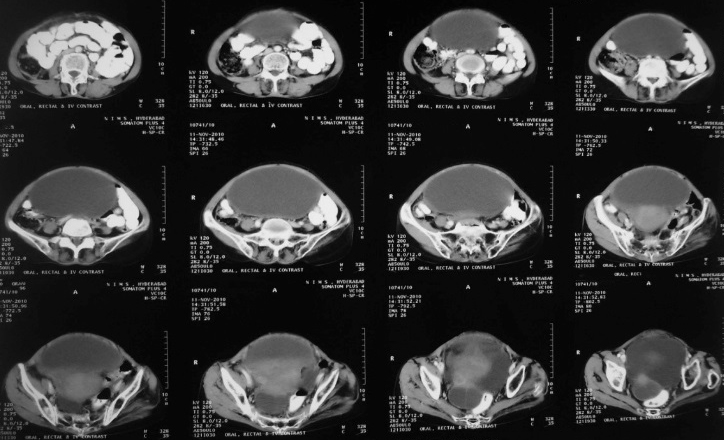

Stage 2: Tumour extends to pelvic soft tissues, or organs in pelvis. In stage 2a extension to uterus and/ or fallopian tube; 2b-extension to other pelvic organs such as bladder, rectum, peritoneum. Bowel or bladder involvement is suggested by loss of fat plane between the organ and mass, encasement or localised thickening. A distance of 3mm between mass and muscle of pelvic side wall or displacement or encasement of iliac vessel is highly suggestive of pelvic side wall invasion; Stage 2c-2a or 2b pluspelvic ascites (Figure 5).

Figure 5: 50y/F - Papillary serous cystadeno carcinoma of ovary. Large solid enhancing component, thick septae pelvic vessels, uterus indicated by arrow stage 2.